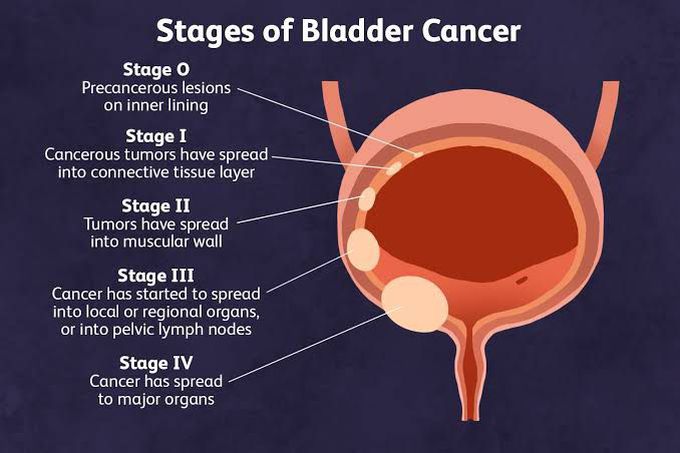

Stages Of Bladder Cancer MEDizzy

Bladder Cancer Stages Royalty Free Vector Image